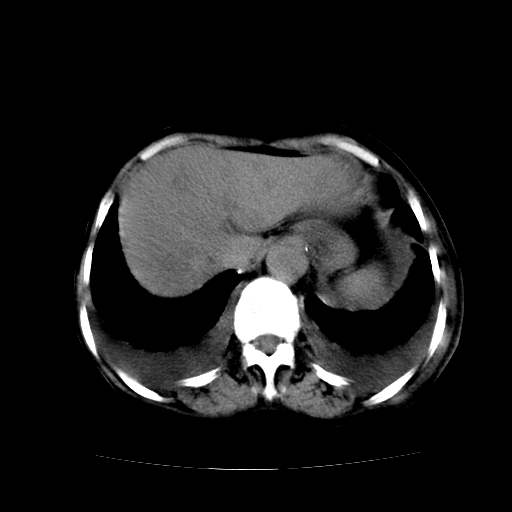

癌性淋巴管炎,肝脏转移,瓷胆囊

1)左侧乳腺癌并左侧腋窝及纵隔淋巴结转移,两肺淋巴道转移(癌性淋巴管炎),肝脏多发性转移。2)双侧胸腔积液。3)慢性胆囊炎。

5、肝转移瘤;

6、瓷胆囊。

1)左侧乳腺癌并左侧腋窝及纵隔淋巴结转移,肝脏多发性转移。2)双侧胸腔积液伴双肺蝶翼样磨玻璃高密度影,双侧肺门血管影增粗(图像不全,肺门层面没纵隔窗),考虑心功能不全所致。3)慢性胆囊炎伴壁钙化。

左侧乳腺癌并左侧腋窝及纵隔淋巴结转移,两肺淋巴道转移(癌性淋巴管炎),肝脏多发性转移。2)双侧胸腔积液。3)瓷胆囊